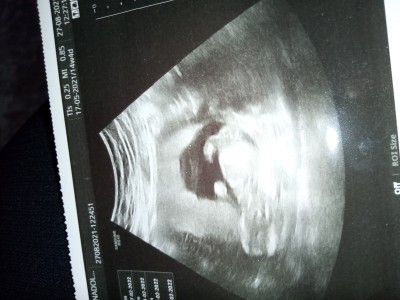

14+4 haftalık hamileyim bugün kontrolüm vardı ama doktor cinsiyetini söylemedi bende çekindim sormaya. Anlayan bayanlar yardımcı olur musunuz cinsiyet konusunda

Gebelik haftası 14+4